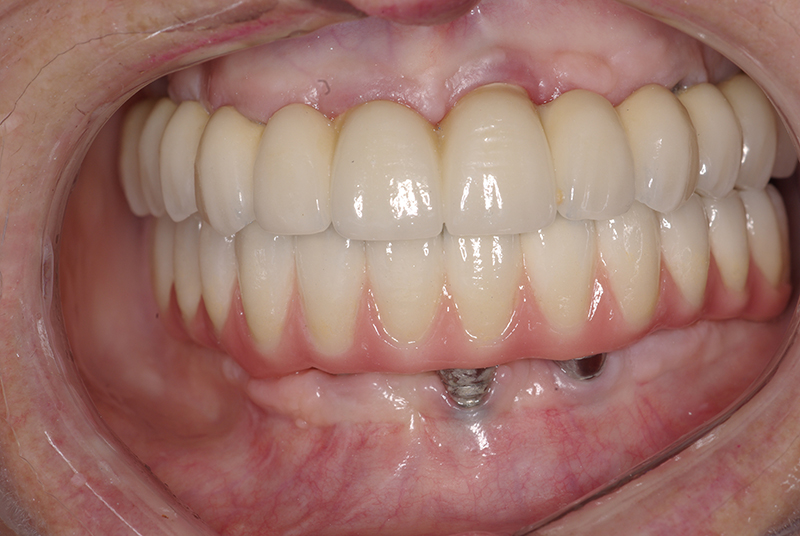

- Recuperação rápida: O paciente sai do consultório com um sorriso renovado em questão de dias.

- Conforto e Estética: A prótese provisória é funcional e visualmente semelhante aos dentes naturais.

- Preservação óssea: A técnica estimula o osso, prevenindo sua reabsorção, comum em casos de perda dentária.

- Melhora da autoestima: O impacto positivo de um sorriso completo é imediato, melhorando a qualidade de vida.